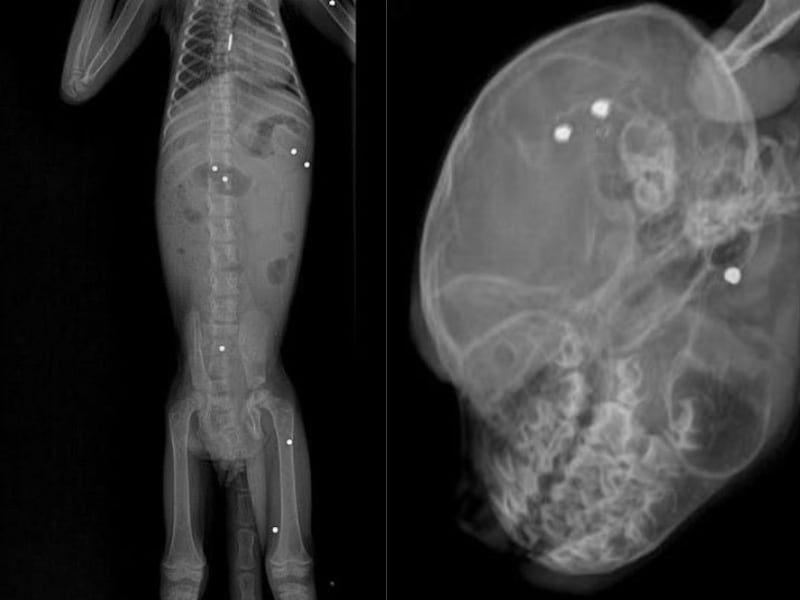

Este ejemplar había sido rescatado en zona rural del corregimiento Puerto Claver, municipio de El Bagre luego de que se le encontraran al animal 19 perdigones dentro de su estructura osteomuscular.

Según explicó el médico veterinario Andrés Rodríguez, durante las ayudas diagnósticas, especialmente en el examen radiográfico, se evidenció la presencia de 19 perdigones alojados en el cuerpo del animal. Estas lesiones, causadas por proyectiles de aproximadamente 3 milímetros de diámetro, afectaron su movilidad (particularmente en una de sus extremidades) y generaron un deterioro progresivo que derivó en su muerte.